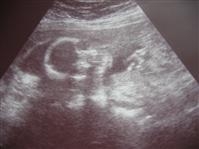

Back from my 20 Wk Ultrasound....

I'm resizing pics as I type...but I'm happy to report we are right on target with how far along I am and how big she is. They think she weighs about 10 ounces.

We reconfirmed that she is a girl and SO NOT SHY about it

She sucked her thumb, had the hiccups, and even flipped from face up to face down. We saw all sorts of different parts of her body which was amazing.

Image Attachment(s):